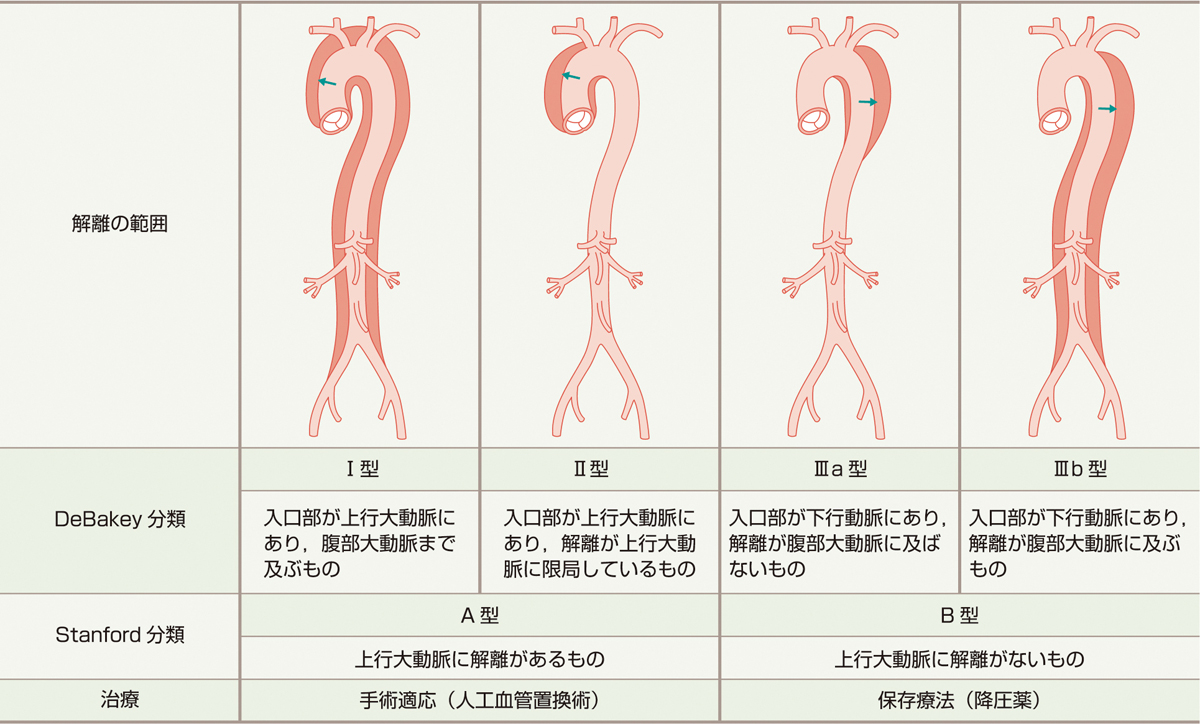

胸部大動脈解離の分類

一般的に,上行大動脈に解離のあるStanford A型は人工血管置換術など手術適応になることがほとんどである (表1,図6).一方,上行大動脈に解離のないStanford B型は降圧薬による保存療法になることがほとんどである.Stanford A型解離では,冠動脈に解離が進行して急性心筋梗塞を併発したり,大動脈弁に解離が及んで大動脈弁閉鎖不全を併発することもある.頸動脈や鎖骨下動脈に解離が及べば,脳梗塞や上肢の麻痺をきたすこともある.このほか大動脈の分枝に解離が及べば,腹部虚血 (アンギーナ) や腎梗塞など,その部位に応じた症状をきたしうる.